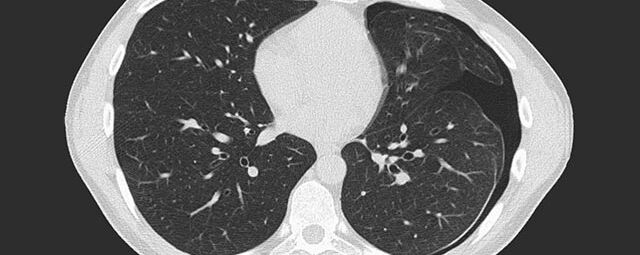

Thorax (Brustkorb)

• Entzündungen oder Tumore des Mediastinums und der Lunge

• Lungenembolie- Diagnostik

• hochauflösende Darstellung des Lungenparenchyms zur Abklärung chronischer interstitieller Erkrankungen wie z. B. Fibrosen, Emphysem, Bronchiektasen